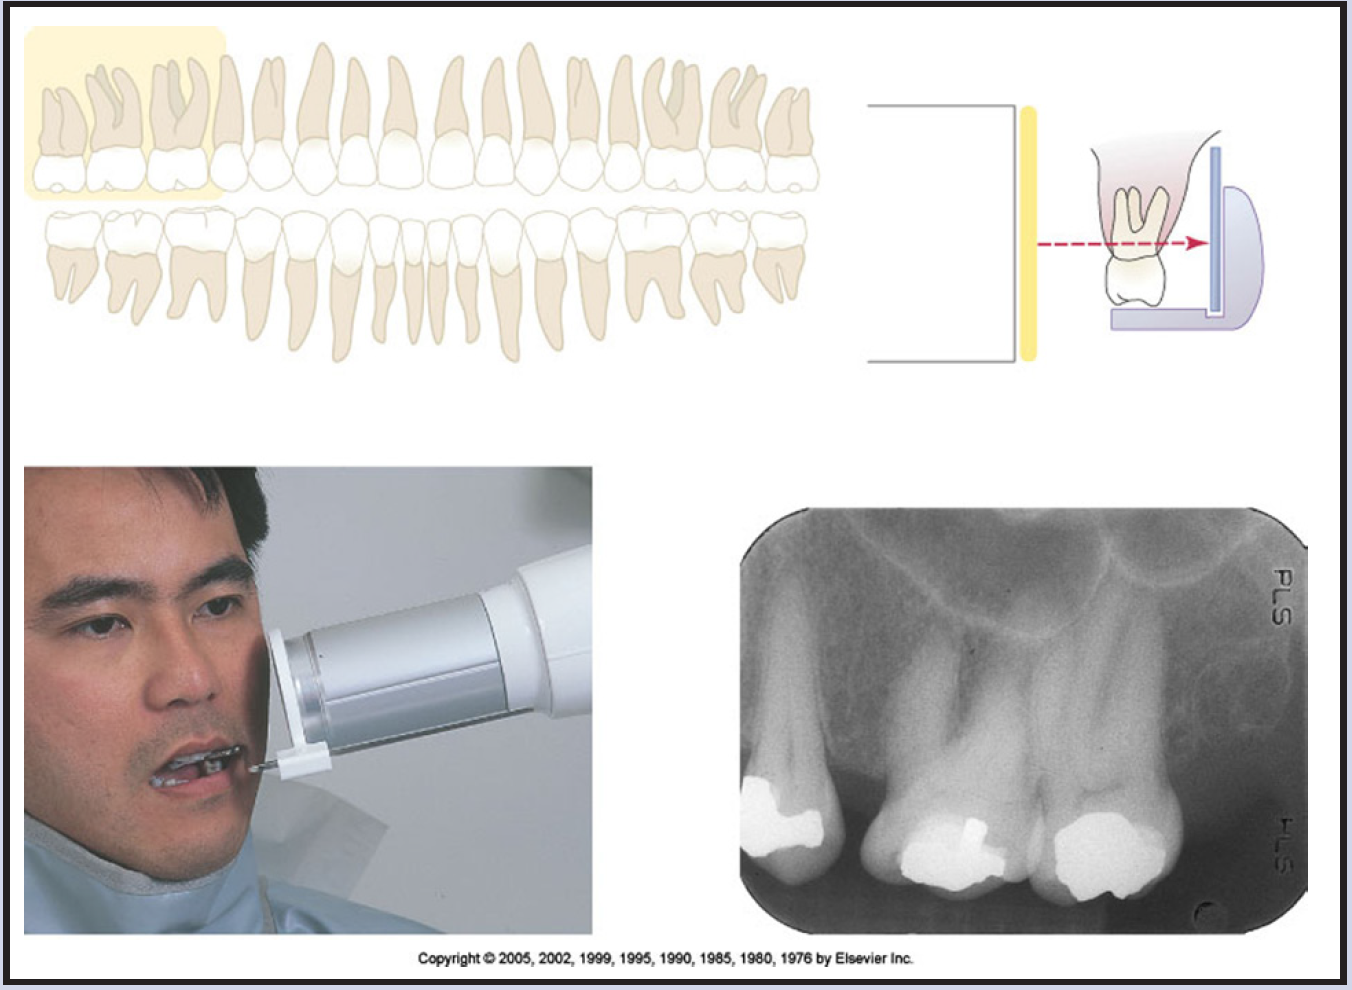

Bitewing Radiography

Bitewing radiographic images are of particular value in detecting interproximal caries in the early stages of development, before it is clinically visible. For this reason, it is critical that horizontal angulation be accurately projected following the direction of the interproximal contacts and no overlapping contacts are present on the radiographic image. Bitewing radiographic images are also useful in evaluation of the alveolar crests for detection of early periodontal disease.

Basic Principles

Bitewing images are parallel images because the receptor is positioned parallel to the long axis of the teeth and the beam is perpendicular to the receptor as in Figure 60. A bitewing tab is utilized to stabilize the receptor as the patient bites together.

Beam Angulation and Receptor Holding Devices

Bitewing radiographic images are usually exposed with an indicated vertical angulation of +10 degrees (tube head points down for positive (+) angulation). This angulation provides an acceptable compromise for the differences between the long axis inclinations of the maxillary and mandibular teeth. Horizontal angulation is aligned with the direction of the contact, and the central ray is directed between the contacts of the teeth to be radiographed. Horizontal angulation is achieved when the central ray of the x-ray beam is directed specifically between the contacts of the teeth to be radiographed.

The interproximal examination may be done using a special type 3 bitewing receptor but is preferably achieved by using four type 2 receptors fitted with a tab. There are also receptor holding devices available that support the receptor as well as provide an external reference for positioning the tube head. The patient stabilizes the receptor by gently biting together on the manufactured tab or on the holding device.

Tube head position is illustrated in Figure 62, and a sample set of bitewing radiographic images is illustrated in Figure 63.